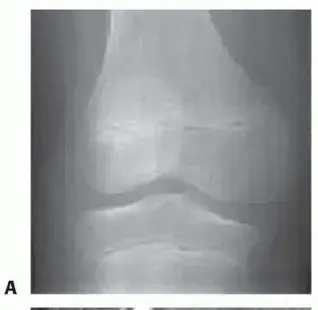

صورة توضيحية لـ الغضروف الهلالي القرصي: دليلك الشامل من التشخيص للعلاج والتعافي مع الأستاذ الدكتور محمد هطيف

3. الأشعة السينية (X-rays):

• عادةً ما تكون الأشعة السينية طبيعية في حالات الغضروف الهلالي القرصي، لأنها لا تظهر الغضاريف بوضوح.

• ومع ذلك، قد يطلب الطبيب الأشعة السينية لاستبعاد حالات أخرى قد تسبب أعراضًا مشابهة، أو لتقييم صحة العظام والمفاصل بشكل عام.